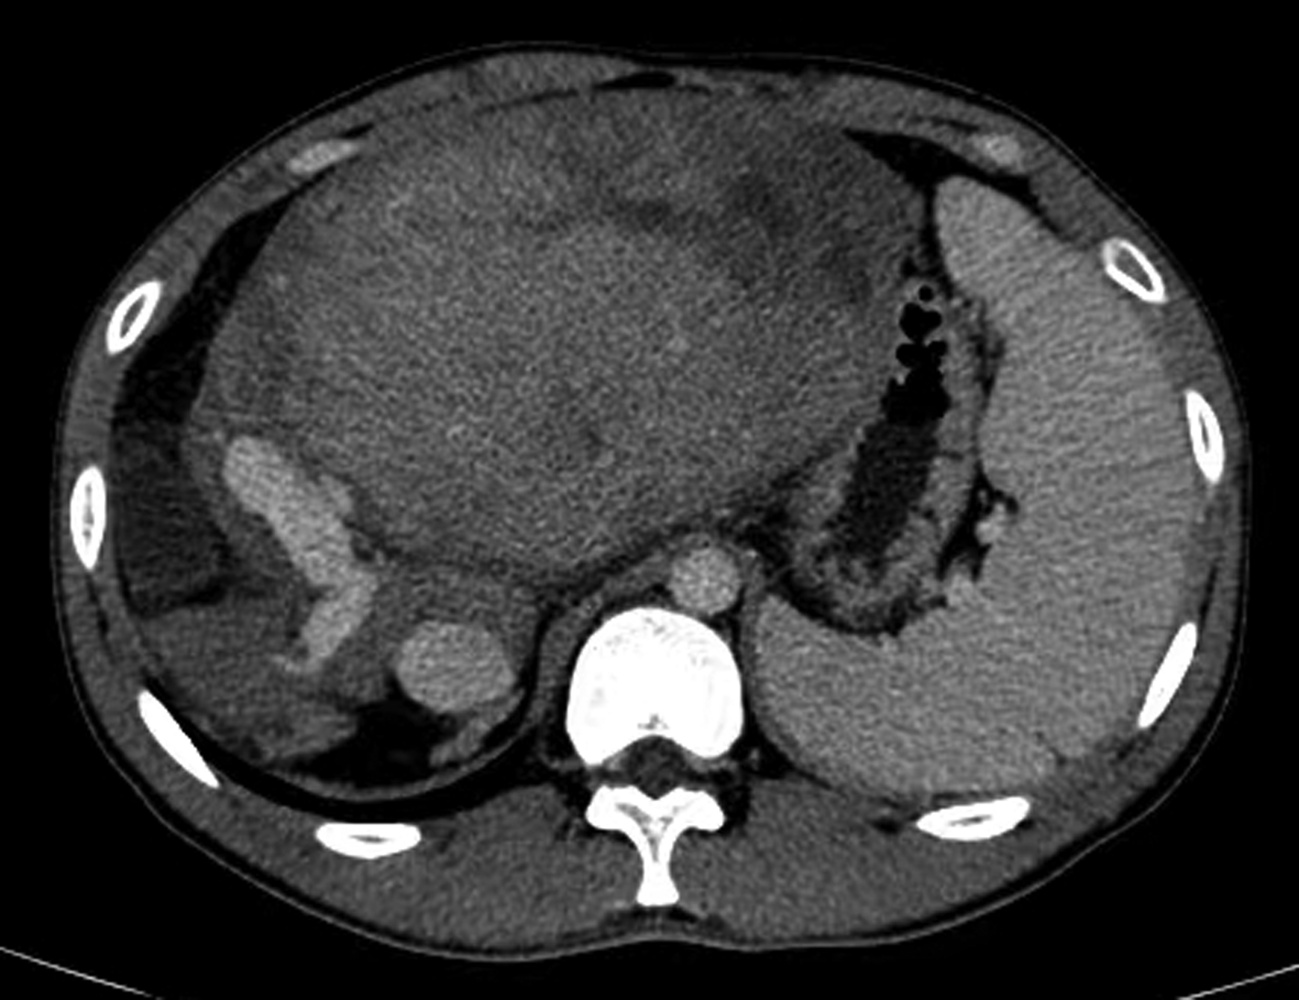

胰管结石治疗方案的选择分析与比较

2022, 38(11): 2558-2564. DOI: 10.3969/j.issn.1001-5256.2022.11.023

摘要(887) HTML (968) PDF (2050KB)(104)

摘要:

目的  收集并对比分析内镜逆行胰胆管造影(ERCP)、腹腔镜术和开腹手术三种方案治疗胰管结石(PDS)患者的临床资料及治疗效果,总结PDS治疗方案选择的经验,进一步研究探讨可行的使患者获益最大化、最优化的治疗方案。  方法  回顾性分析2014年6月—2018年12月海军军医大学附属公利医院治疗的131例PDS患者的临床资料。根据手术情况分为3组:ERCP组69例,腔镜组32例,开腹组30例。监测3组患者手术前后相关指标的变化;进一步对比分析腔镜组和开腹组的手术疗效。正态分布的计量资料两组间比较采用独立样本t检验;多组间比较采用单因素方差分析,进一步两两比较采用LSD-t检验或SNK-q检验。偏态分布的计量资料两组间比较采用Mann-Whitney U检验,多组间比较采用Kruskal-Wallis H检验。手术前后相关指标差异比较采用重复测量资料的方差分析和Friedman检验。计数资料组间比较采用χ2检验。  结果  131例PDS患者中Ⅰ型40例、Ⅱ型76例、Ⅲ型15例。腔镜组与开腹组主要手术方式的病例数比较差异无统计学意义(χ2=1.93,P>0.05)。腔镜组和开腹组血WBC、CRP、PCT、HOMA-IR在手术前后的动态变化存在明显差异(F=24.68、χ2=227.66、F=45.37、F=106.71,P值均<0.05)。腔镜组手术时长、术中出血量、术后首次排气时间、术后止痛药物应用频次、腹腔引流管拔除时间、术后近期并发症、术后平均住院时长等观察指标均较开腹组明显减少/缩短(t=-4.80、t=-9.43、Z=-6.78、t=-11.59、Z=-6.77、χ2=9.24、t=-3.60,P值均<0.05)。ERCP组、腔镜组、开腹组术后近期并发症发生率分别为24.64%、28.13%、66.67%,差异有统计学意义(χ2=17.12,P<0.05);ERCP组及腔镜组术后近期并发症发生率均显著低于开腹组(χ2值分别为15.78、9.24,P值分别为<0.05、0.02)。ERCP组、腔镜组、开腹组治疗有效率分别为91.30%、93.75%、73.33%,3组间有效率差异有统计学意义(χ2=7.70,P=0.02),ERCP组及腔镜组有效率均好于开腹组(χ2值分别为5.56、4.77,P值分别为0.02、0.03)。  结论  ERCP为临床微创治疗部分Ⅰ、Ⅱ型PDS的首选治疗方法,安全有效、严重并发症少。外科手术是治疗复杂型PDS的重要手段,但技术复杂、操作难度大。腹腔镜术较开腹术创伤小、严重并发症少,腹痛缓解率高,可以显著减少手术时长、降低术中出血量及缩短术后平均住院时长。针对复杂型PDS宜优先选择腹腔镜术治疗。